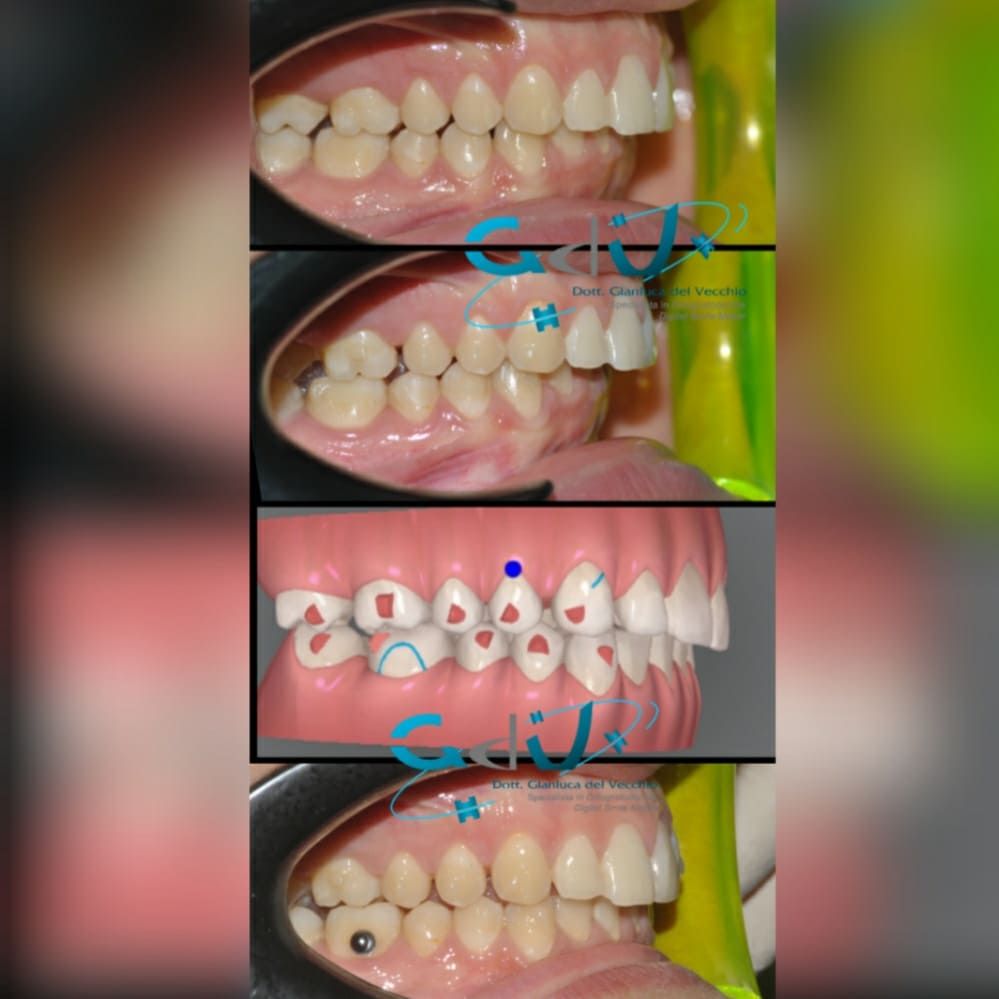

Il dottore ha acquisito una concezione quanto più pratica e moderna della disciplina e utilizza apparecchietti di diversi colori di tipo mobile e fisso, ma anche terapie sia estetiche che invisibili, fiore all’occhiello di poche realtà in Italia. Per terapie estetiche e invisibili si intendono quelle in grado di spostare i denti, senza che traspaia nulla dalla bocca o con stelline e fili bianchi, esattamente come i denti del paziente.

Ma ancora di più l’équipe è in grado di offrire un servizio davvero unico: la tecnica dei retainer attivi. Questa consiste in fili o bottoni che si incollano dietro i denti e che, quindi, nascondono completamente la terapia. Questo tipo di prestazioni aiuta a superare la grande difficoltà psicologica, che spesso si insinua anche negli adulti, di dover spostare i propri denti per un sorriso perfetto: si consideri che tale difficoltà non viene affrontata, il più delle volte, proprio per l’imbarazzo che una apparecchiatura ortodontica genera in chi la usa. Queste tecniche, insieme alle mascherine invisalign invisibili di cui è provider ufficiale e agli attacchi in ceramica, sono tutte quotidianamente utilizzate presso i nostri reparti, in cui è possibile associarle in un discorso multidisciplinare a tutte le altre esigenze della odontoiatria classica.